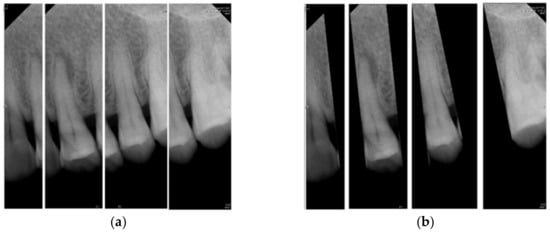

2.1.1. Vertical Cutting

2.1.2. Image Masks